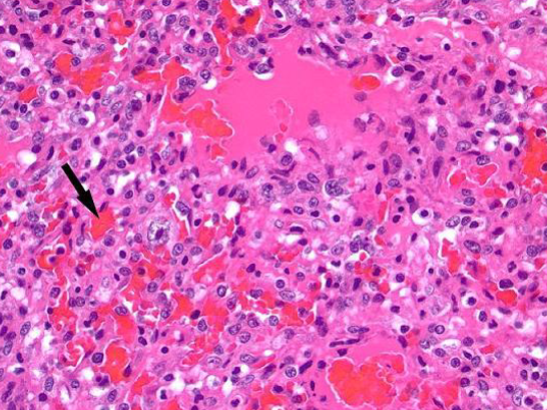

How does vasculitis appear histologically?

Fibrinoid necrosis (indicated vascular damage)

Inflammation of the intima and media

Leukocytes present within and surrounding walls

Endothelial damage causes thrombosis → infarction